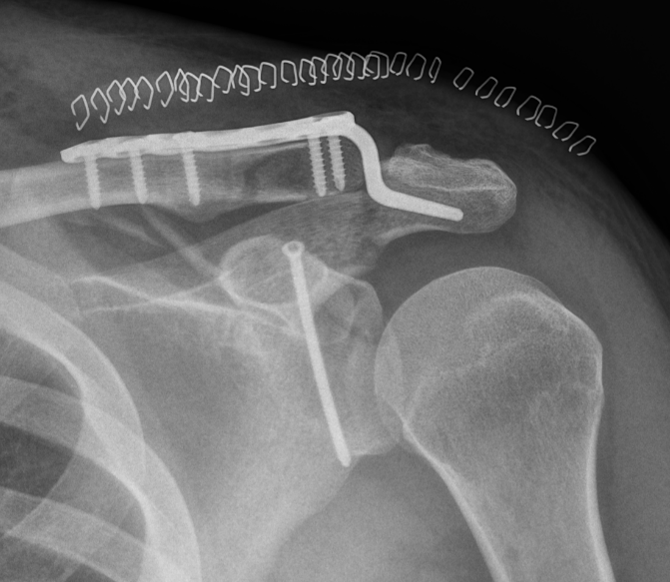

Scapular neck fracture with clavicle fracture